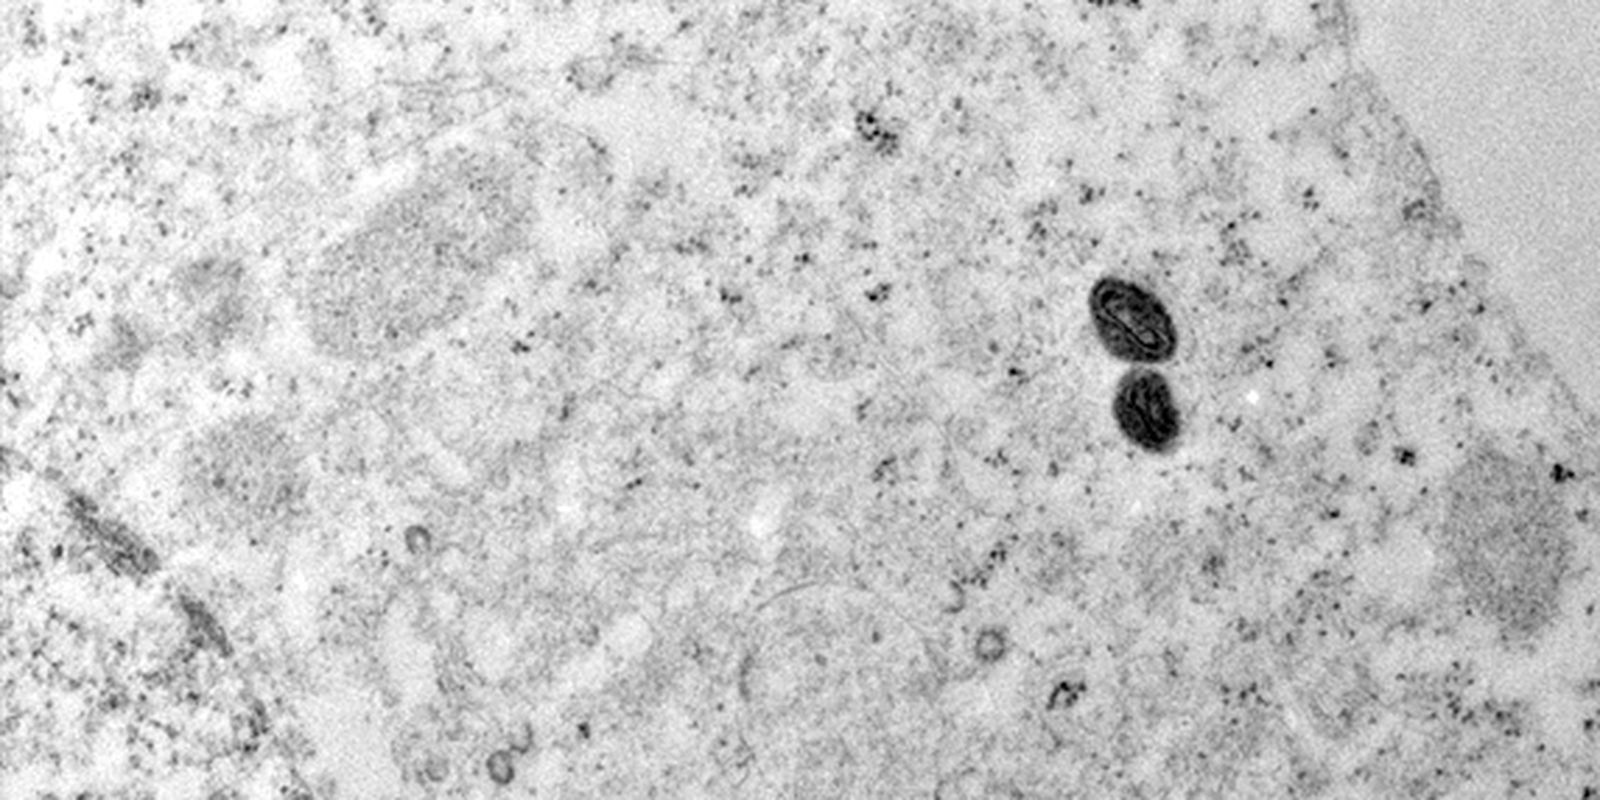

O Ministério da Saúde da Argentina descartou a suspeita de mpox em um tripulante de navio que saiu do Brasil e permanecia em quarentena no país vizinho. “Após exames laboratoriais, as autoridades de vigilância sanitária argentinas confirmaram que se tratava de varicela”, informou o Ministério da Saúde do Brasil, em nota.

No comunicado, o governo brasileiro reforçou que a variante 1b da mpox, que levou a Organização Mundial da Saúde (OMS) a declarar emergência em saúde pública de importância internacional, não está em circulação no Brasil. Em 2024, o país confirmou 791 casos da doença, mas todos da variante 2b, já conhecida.